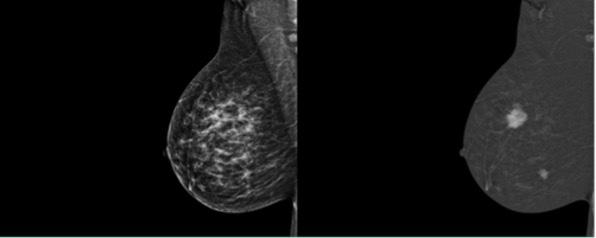

Tout savoir 45 sur l’angio-mammographie

Comprendre cette technique et son application concrète en milieu clinique